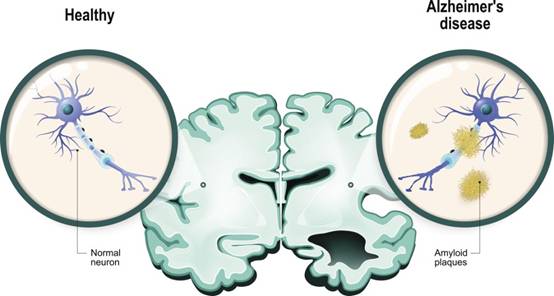

AD作为一种起病隐匿的复杂异质性疾病,其特征性的改变主要为β淀粉样蛋白沉积形成的细胞外老年斑和神经细胞内神经原纤维缠结。除此之外,还有皮质弥漫性萎缩、脑沟回增宽、脑室扩大、神经元大量减少等病变。

图2 健康脑的神经元(左)和患病脑的神经元(右)(图片来源:veer图库)

AD患者大脑的一个重要特征是神经元大量减少。基于此特征,也有科研人员致力于通过训练或者药物刺激神经元新生来预防和治疗AD。我们都知道,人体的大部分器官都会有细胞的衰亡,也不断有新细胞的产生,比如肝脏的细胞再生能力就很强。然而关于成人大脑中是否存在新生神经元则一直存在争议。